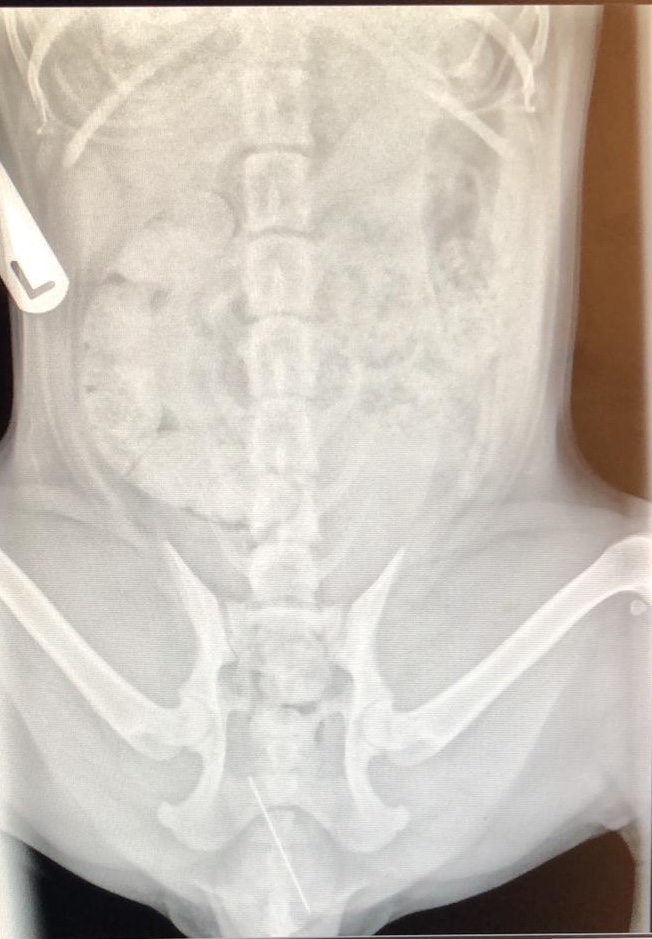

After Poppy was sedated an abdominal radiograph was performed and revealed a sewing needle was indeed attached to the end of the string! This is evident within the radiographs below. This was successfully removed and Poppy was sent home later that day with pain relief. We are pleased to report she made a full recovery.